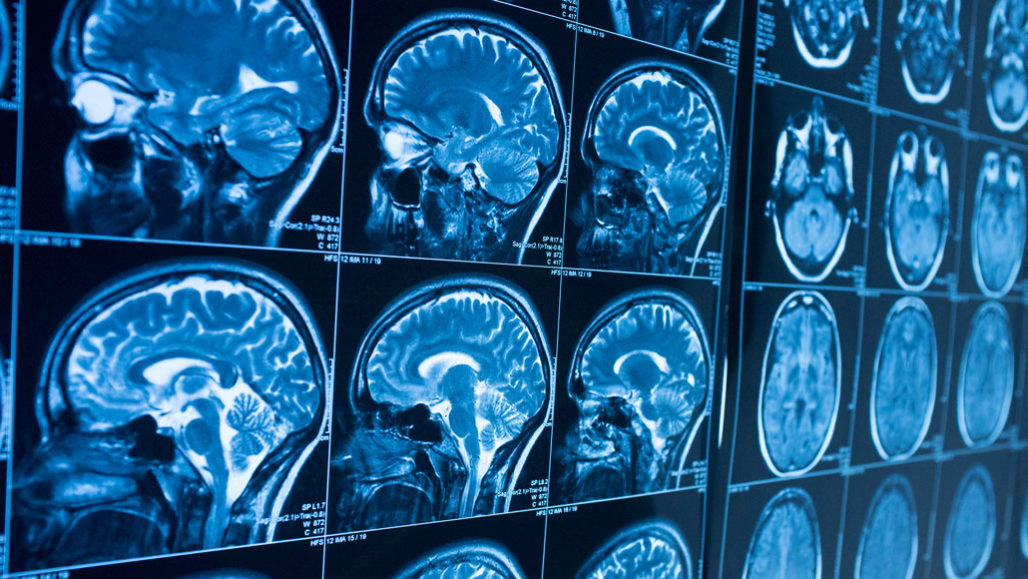

One or two seconds before people recall an image they had previous seen, cells in a key memory center in the brain fire together, creating a “ripple” of activity.

Movus/iStock/Getty Images Plus